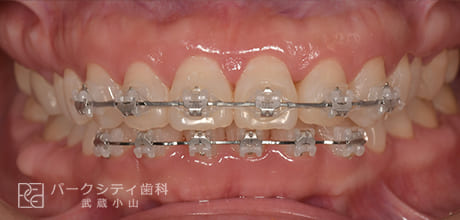

CASE.02

表側の部分矯正の症例

術前

術中1か月

術中3か月

4か月

- 主訴

- 前歯の隙間が気になる

- 治療法

- 表側の部分矯正

- 治療期間

- 4か月

- 費用

- ¥413,600

【内訳】

検査料:¥33,000

装置料:¥165,000×2(上下)

チェック:¥4,400×4

保定装置:¥16,500×2(上下)

上下表側に装置をつけ、隙間を閉じながら歯並びを整えて、約4か月で保定へ移行しました。